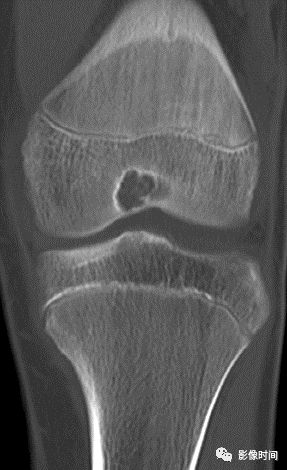

(一)瘤软骨钙化:瘤软骨常表现为环状钙化, 是诊断软骨类肿瘤较为可靠的影像学征象。环状钙化形成于环状软骨、以及软骨小叶边缘的软骨基质。钙质沉着可呈小点状、小条状、半环状或弧形;亦可浓密相连、重叠呈菜花状。钙化环的形态和密度可反映瘤组织分化程度, 通过观察钙化环的形态和密度,有助于良恶肿瘤的鉴别。

良性瘤软骨之瘤细胞分化好、生长缓慢、血供充分, 钙化环完整,密度高, 边缘清楚。良性软骨类肿瘤如骨软骨瘤(图 35)、软骨母细胞瘤(图 36)、内生软骨瘤(图 37)等均可于瘤组织内发生环形钙化。

恶性瘤软骨则呈密度淡薄, 边缘模糊的不规则钙化,恶性骨肿瘤的环形钙化,最多见于软骨肉瘤(图 38),其次是骨肉瘤。CT 是发现肿瘤内软骨钙化最为敏感的检查方法。

图 36  瘤软骨钙化:软骨母细胞瘤